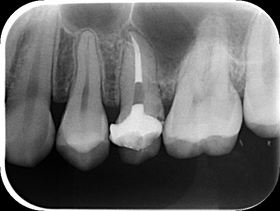

下のエックス線写真は、強い自発痛を訴えて来院された患者さん。

臨床ではよく遭遇する、2次カリエスからの歯髄炎(歯の神経の炎症)を引き起こしています。

写真上で白く写っている金属の詰め物と歯の境目から2次的に虫歯になり、歯の内部にまで進行してしまった結果です。

写真をみると、根管内に白いものが認められると思います。これが、ガッタパーチャを充填した状態です。

根尖部で分岐している側枝にも、しっかり根管充填ができました。